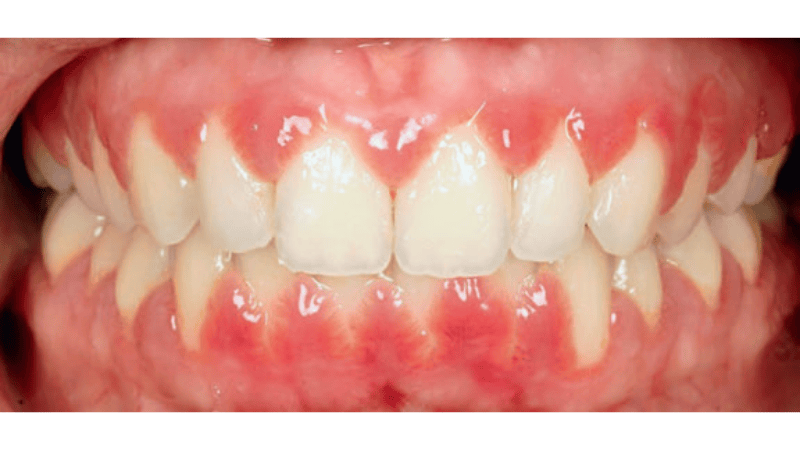

Streszczenie: Powiększenie dziąseł wywołane lekami (DIGO – drug-induced gingival overgrowth) jest postacią zapalenia dziąseł wywołanego przez biofilm nazębny. Stanowi ono częste powikłanie przewlekłej terapii lekami przeciwpadaczkowymi, blokerami kanałów wapniowych oraz lekami immunosupresyjnymi. Prezentowany opis przypadku dotyczy 24-letniej pacjentki, która od czterech lat przyjmuje lek immunosupresyjny (cyklosporynę A) z powodu przewlekłego kłębuszkowego zapalenia nerek. Objawy w jamie ustnej o charakterze powiększenia dziąseł dotyczyły głównie okolicy zębów siecznych. Leczenie obejmowało korektę sposobu szczotkowania zębów w domu, leczenie niechirurgiczne (etap nadi poddziąsłowy) i gingiwektomię.

Summary: Drug-induced gingival overgrowth (DIGO) is a form of gingivitis caused by dental biofilm. It is a common complication of chronic therapy with antiepileptic drugs, calcium channel blockers and immunosuppressants. This case report presents a 24-year-old female patient who has been taking an immunosuppressive drug (cyclosporine A) for four years due to chronic glomerulonephritis. The oral symptoms in the form of gingival enlargement mainly affected the incisal teeth area. Treatment included the [...]